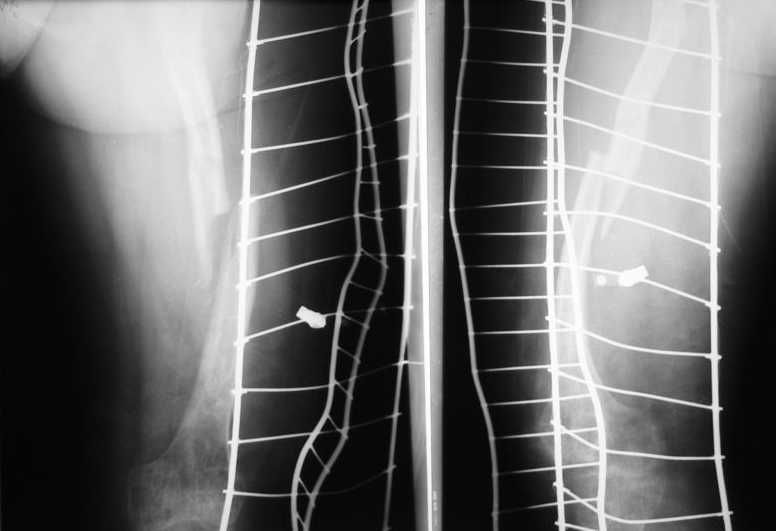

Поступила пациентка 20 лет с патологическим переломом бедра в С/З, находилась под наблюдением детских ортопедов по поводу незавершенного остеогенеза с рождения. За последний год перелом бедра был уже дважды, лечилась консервативно на вытяжении.На сегодняшний день имеется вот такая картина. Бедро деформировано на всем протяжении, остеопороз, участки остеосклероза. Уважаемые коллеги, какие будут соображения по тактике лечения. С уважением Леонид

На этих снимках не очень хорошо видно структуру кости на всем протяжении. Видимо, попытаться сформировать канал при наличии инструментов типа очень длинного шила, лучше нескольких, разных диаметров, можно было бы. Мы такие инструменты себе сделали сами.

Еще одна проблема - ось бедра не на всем протяжении будет совпадать с осью гвоздя. Хотя канал можно и кривой сформировать, гвоздь в него потом не ввести. Это более менее легко решается чрескожной остеотомией или несколькими, прямо по ходу введения гвоздя.

Если какой-то участок полностью заращен и деформирован, можно его продольно расщепить.

В общем, штифтование в этом случае было бы непростой и нестандартной операцией.

Вариант с пластинкой тут вполне имеет шансы на успех.